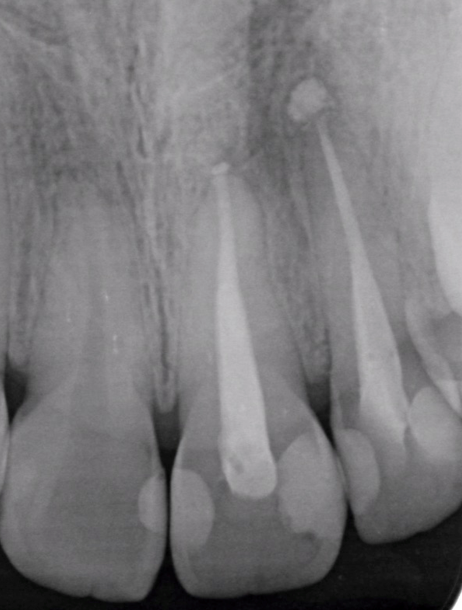

症例4

治療経過

①![]() 術前 |

②![]() 根管治療後3か月経過 |

③![]() 根管治療後1年経過時 |

④![]() 根管治療後2年経過時 |

神経の治療後、①→②→③→④と時間をかけて徐々に治ってくることがあります。

神経の治療は細菌感染を除去する治療です。細菌がいなくなれば、無駄に神経をとらなくても良い歯もあるかもしれません。

レントゲン検査や患者様の訴える症状だけでは神経を残せるかどうかは断定できません。 この方もレントゲン写真上では神経を残せないように見える歯でしたが、治療前に検査を入念に行うことで残せる可能性を見出すことができました。 同じ悩みを抱えた方は是非お気軽にご相談下さい。 |